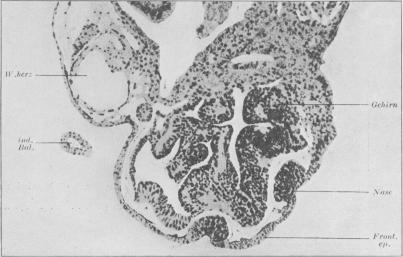

Needham J

Proc R Soc Med. 1936 Oct;29(12):1577-626. doi: 10.1177/003591573602901209.